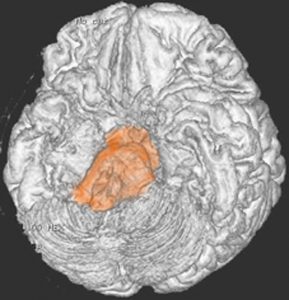

脳幹部の解剖図

- 脳の底面からしか見えないのでいろいろな角度から見ています